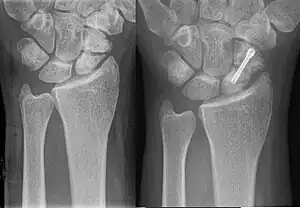

Nonunion is permanent failure of healing following a broken bone unless intervention (such as surgery) is performed. A fracture with nonunion generally forms a structural resemblance to a fibrous joint, and is therefore often called a "false joint" or pseudoarthrosis (from Greek pseudo-, meaning false, and arthrosis, meaning joint). The diagnosis is generally made when there is no healing between two sets of medical imaging, such as X-ray or CT scan. This is generally after 6–8 months.[1]

Signs and symptoms

A history of a broken bone is usually apparent. The patient complains of persistent pain at the fracture site and may also notice abnormal movement or clicking at the level of the fracture. An x-ray plate of the fractured bone shows a persistent radiolucent line at the fracture. Callus formation may be evident but callus does not bridge across the fracture. If there is doubt about the interpretation of the x-ray, stress x-rays, tomograms or CT scan may be used for confirmation.

Hypertrophic non-union

Callus is formed, but the bone fractures have not joined. This can be due to inadequate fixation of the fracture, and treated with rigid immobilisation.

Diagnosis

The diagnosis of nonunion is generally done when there is no progress between two occasions of medical imaging such as X-ray. This is generally the case after 6–8 months.[1]